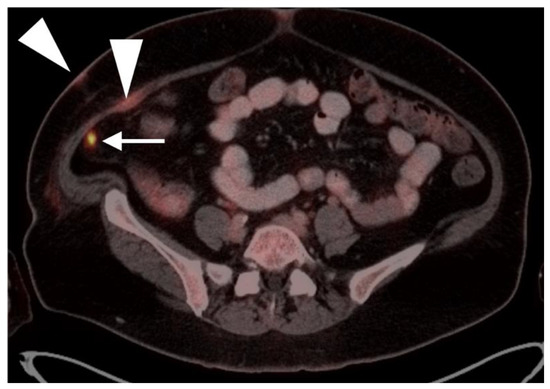

2.6. Vulvar Carcinoma

2.7. Considerations of Pregnancy

3.5. Penile Cancer